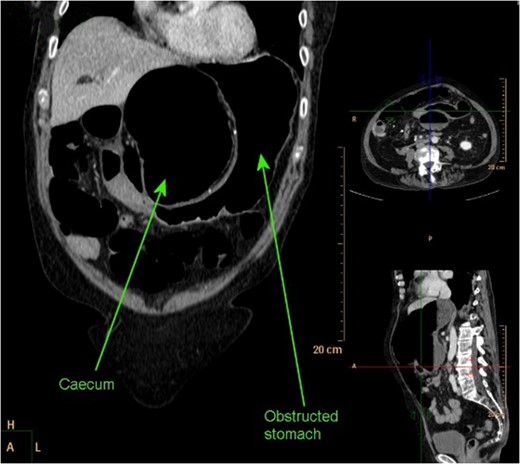

CT abdomen coronal reconstruction demonstrating obstructed stomach with obstructed and dilated caecum present in lesser sac.

Axial section of CT abdomen demonstrating NG tube in stomach, with successful decompression of obstructed gastric outlet, however obstructed caecum clearly visible within lesser sac.